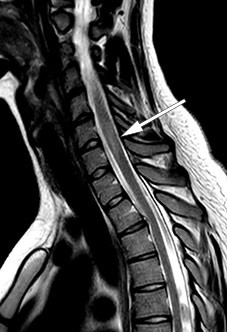

A follow-up MRI one month later showed a new non-enhancing lesion in the right thalamus (Figure 2) as well as two new, small, enhancing lesions in the medulla at C5, C6 and possibly also Th5. The infratentorial lesions had resolved completely, and those in the medulla oblongata were reduced.

Figure 2 Right thalamic lesion on coronal MRI with FLAIR (fluid-attenuated inversion recovery).